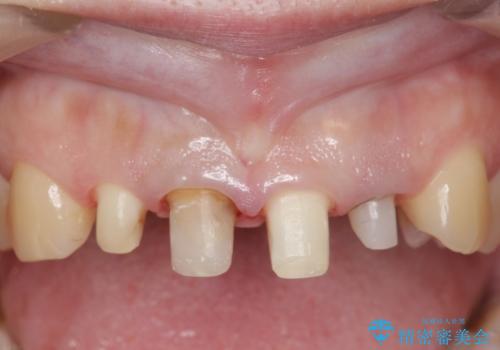

- 前歯の色や長さ、歯茎との隙間の金属が気になるのでセラミックで治療したいといらっしゃった方の症例です。

見た目改善のため、前歯4本をオールセラミッククラウン(スペシャル)で補綴しました。

右上1と左上2は再根管治療を行っております。